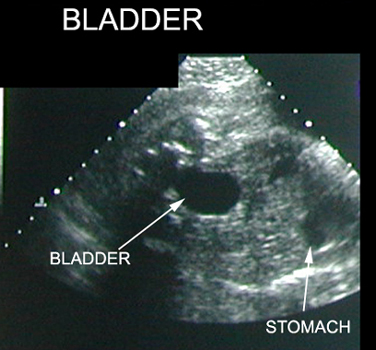

38 Weeks of Intrauterine Pregnancy |

|

|

|

|

|